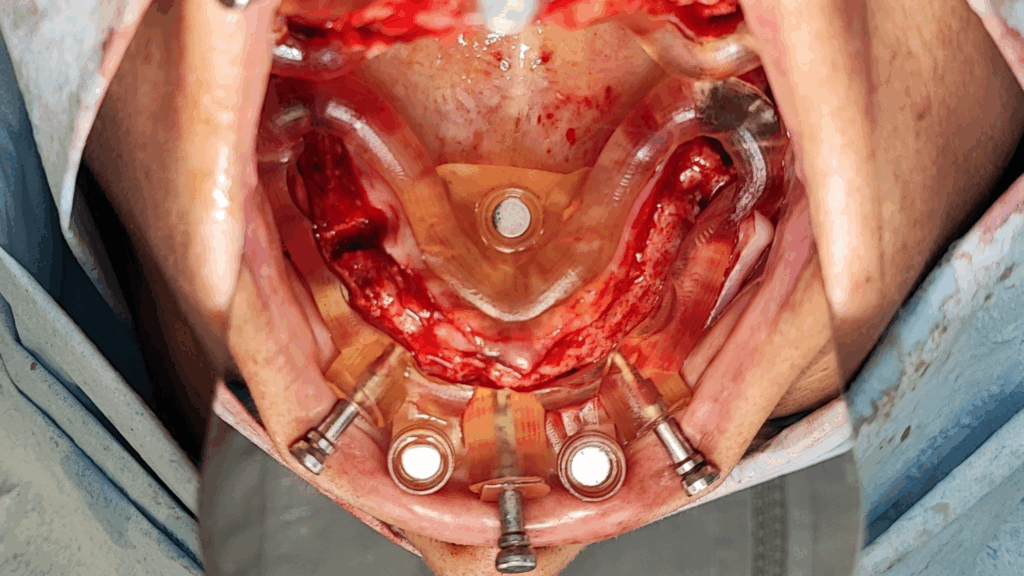

Rehabilitación completa maxilar (Full Arch)

Paciente: mujer, 59 años, edentulismo parcial.

Tratamiento: colocación de 6 implantes inmediatos con férulas apilables y prótesis provisional instantánea parcial.

Tiempo de intervención: 2 horas y 30 minutos.

Beneficios: intervención rápida y precisa, manejo conservador del tejido blando, estética y funcionalidad instantánea, alta satisfacción del paciente.

Estos casos ilustran cómo nuestro flujo BRDP y la cocreación clínica permiten resultados predecibles y eficientes, optimizando tanto el tiempo de sillón como la experiencia de paciente y clínica.